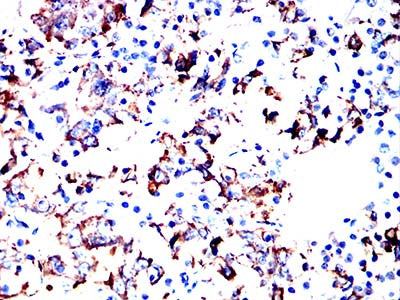

- Immunohistochemical analysis of paraffin-embedded human hypophysis tissues using PRL mouse mAb with DAB staining.